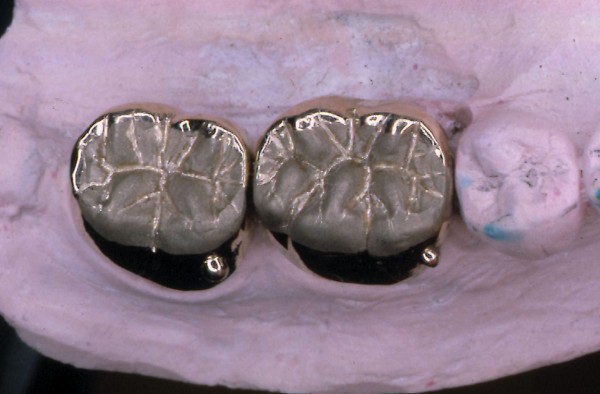

MUCHO SE HA HABLADO HASTA HOY DE LOS DISTINTOS ESQUEMAS OCLUSALES A USAR. SIN EMBARGO , HAY ALGO DE QUE ADOLECEN LAS LOS TRABAJOS PROTÉTICOS OBSERVADOS EN MÚLTIPLES LABORATORIOS DE NUESTRO MEDIO , COMO ASI DE MUCHAS PUBLICACIONES DE LOS ÚLTIMOS TIEMPOS , OLVIDANDO UN CONCEPTO TAN BÁSICO COMO EVIDENTE: PARA QUE SIRVEN LOS DIENTES. OBSERVAMOS A MENUDO GRANDES ELEVACIONES DE SENO A FIN DE LOGRAR IMPLANTAR LO IMPOSIBLE….LATERALIZACIONES DE NERVIO DENTARIO INFERIOR CON FINES SIMILARES…EXTENSAS PRÓTESIS CANTILEVER PARA REPONER LA CASI TOTALIDAD DE UNA ARCADA…Y UN SINFÍN DE RECURSOS QUE SE ACERCAN AL CRITERIO DE «ALGO HAY QUE PONER…» Y SE ALEJAN DEL SERIO SENTIDO DE «REHABILITAR». SABEMOS QUE SON MÚLTIPLES LAS FUNCIONES QUE EL SISTEMA DENTARIO CUMPLE, PERO LA FUNDAMENTAL ES MASTICAR. EN ESE SENTIDO DESDE LOS RUMIANTES, HASTA LOS CARNÍVOROS TIENEN SUS PROPIOS PATRONES A SEGUIR. EN EL CASO DEL HOMBRE, CON UNA ARTICULACIÓN TEMPOROMANDIBULAR TAN COMPLEJA Y PAUSIBLE DE DISFUNCIONES, COMO DE UN COMPLEJO MUSCULAR NECESITADO DE UNA LONGITUD ADECUADA PARA SU ORTOFUNCIÓN, LA CAPACIDAD DE MASTICAR SE VE A MENUDO ALTERADA POR LOS INNUMERABLES TRABAJOS PROTÉTICOS QUE A DIARIO SE REALIZAN EN EL MUNDO, QUE CARECEN DE LOS PATRONES NECESARIOS PARA QUE ESA FUNCIÓN SE DESARROLLE CORRECTAMENTE. LAS SUBFUNCIONES DE : INCIDIR-DESGARRAR-DISCERNIR EL ALIMENTO Y MOLER, ,PARA FINALMENTE DEGLUTIR, QUE CUMPLEN LAS DISTINTAS PIEZAS DENTARIAS , CONSTITUYEN UN CAPÍTULO DE LA ODONTOLOGÍA TAN BÁSICO Y EVIDENTE, COMO OLVIDADO . ES A MI CRITERIO FUNDAMENTAL ; PENSAR LAS DISTINTAS REHABILITACIONES ORALES POSIBLES, EN TÉRMINOS DE : EFICACIA MASTICATORIA CUANDO A MENUDO OBSERVAMOS CARAS PALATINAS DE LOS ANTERIORES CLARAMENTE CONVEXAS, O CUANDO LAS SUPERFICIES OCLUSALES DE LOS POSTERIORES SE CONSTRUYEN CON CÚSPIDES GRADO CERO, CON FINES DE MINIMIZAR LAS FUERZAS EXPULSIVAS DE UNA PRÓTESIS O LAS FUERZAS TANGENCIALES A LOS IMPLANTES, …LA EFICACIA MASTICATORIA, DISMINUYE SENSIBLEMENTE , CUANDO NO SE PROVOCAN DISFUNCIONES IATROGÉNICAS A VECES MAS DIFÍCILES DE RESOLVER QUE EL ESTADO INICIAL DE LA BOCA. DE LA MISMA MANERA, LA CONSERVACIÓN PROLONGADA DE PIEZAS EN ESTADO TERMINAL, MUCHAS VECES PROVOCA LA PÉRDIDA EXAGERADA DE HUESO ALVEOLAR, MANTENIENDO LOS MISMOS CON SUPRAESTRUCTURAS QUE AGRAVAN LA SITUACIÓN. SI BIEN ES CIERTO, QUE LA CONSERVACIÓN DE PIEZAS DENTARIAS , MUCHAS VECES EN «ESTADO CAÓTICO», NOS SIRVEN PARA SOPORTAR ELEMENTOS PROVISIONALES DE ALTA EFICACIA DURANTE EL TRATAMIENTO REHABILITADOR….Y QUE LAS MISMAS ADQUIEREN ESTADOS MUCHO MAS BENÉFICOS DURANTE SU PROVISORIA FUNCIÓN, TAMBIÉN ES CIERTO, QUE CON VISTAS A UNA MAYOR «EFICACIA MASTICATORIA», LA CONSERVACIÓN DEL HUESO RESIDUAL POST EXTRACCIÓN, ADECUADAMENTE TRATADO , SUELE SER DE MAS UTILIDAD , QUE LA CONSERVACIÓN PROLONGADA DE ELEMENTOS DENTARIOS ALTAMENTE DESTRUIDOS. SALZMAN, EN 1.947 COMPROBÓ QUE PUEDE NO EXISTIR EL MOVIMIENTO HORIZONTAL MANDIBULAR DURANTE LA MASTICACIÓN DE ALIMENTOS BLANDOS, MIENTRAS QUE LOS ALIMENTOS DUROS QUE NECESITAN MAS PRESIÓN, DAN FORZOZAMENTE LUGAR A LA TRANSTRUSIÓN. JANKELSON, HOFFMAN Y HENDRON, EN 1.953, ESTABLECIERON QUE LA MASTICACIÓN, BILATERAL ALTERNADA, ERA NECESARIA PARA LA MANUTENCIÓN DE LAS ESTRUCTURAS DE SOPORTE, Y QUE LAS MASTICACIONES UNILATERALES O PROTRUSIVAS ERAN PRODUCTO DE INTERFERENCIAS OCLUSALES. CIERTOS ESTUDIOS REALIZADOS CON CINEFLUOROSCOPÍA HAN DEMOSTRADO QUE NO EXISTE NINGÚN CONTACTO DENTARIO DURANTE LA MASTICACIÓN . NO OBSTANTE ADAMS Y ZANDER EN 1.964, CON MÉTODOS DE BASADOS EN LA MULTIPLICIDAD DE ESTUDIOS PRODUCIDOS ACERCA DE LA FISIOLOGÍA DE LA MASTICACIÓN , ES IMPENSABLE HOY, A LA ALTURA DE LOS CONOCIMIENTOS ACTUALES , ESCAPAR A LA NORMA INELUDIBLE DE FORMA = FUNCIÓN POR ELLO ES NECESARIO , ANALIZAR LAS REHABILITACIONES EN FORMA GLOBAL E INTESIVAMENTE , YA QUE , POR EJEMPLO , LA SIMPLE INSTALACIÓN DE IMPLANTES DENTALES , POR MUY INTEGRADOS QUE ESTEN , DE NADA SIRVEN SI NO EXISTE UNA CONGRUENCIA ENTRE LAS FORMAS QUE CUMPLAN LAS FUNCIONES ESPECÍFICAS PARA LAS CUALES HA SIDO CREADO EL SISTEMA. EN LAS SIGUIENTES FOTOGRAFÍAS PERTENECIENTES A UN MISMO CASO , SE OBSERVA CLARAMENTE QUE SI BIEN SE HAN COLOCADO LAS PIEZAS FALTANTES EN UN ÁREA EDÉNTULA , DE POCO SERVIRÁN YA QUE LA GUIA CANINA DEL LADO OPUESTO ES INEXISTENTE, ADEMÁS DE QUE LAS SUPERFICIES OCLUSALES DIFÍCILMENTE CUMPLAN CON LA EFICACIA MASTICATORIA. EN LA MASTICACIÓN OMNÍVORA LOS CONTACTOS OCLUSALES SON INEXISTENTES SALVO EN LA ÚLTIMA FASE DEL CICLO MASTICATORIO. EL CICLO MASTICATORIO CONSTA DE DISTINTAS FASES DE LAS CUALES LA INICIAL , CONSISTE EN LA: POSTERIORMENTE , LA MANDIBULA EJERCE UN MOVIMIENTO LATERAL HACIA EL LADO (LADO DE TRABAJO) DONDE SE HA UBICADO EL ALIMENTO : A CONTINUACIÓN LA MANDIBULA LATERALIZADA COMIENZA EL CIERRE , HASTA CONTACTAR LOS CANINOS ENTRE SI : DONDE EL SUPERIOR SEÑALA EL CAMINO A SEGUIR DEL CANINO INFERIOR (QUE ES SOLIDARIO A LA MANDIBULA TODA), DESDE EL PUNTO DEL PRIMER CONTACTO (BORDE A BORDE CANINO , O SUS CERCANÍAS ), HASTA AQUEL PUNTO TERMINAL ,DEL RECORRIDO CANINO QUE SEÑALA LA: …….. DEL RESTO DE LAS PIEZAS. DURANTE ESA APROXIMACIÓN HACIA LA MÁXIMA INTERCUSPIDACIÓN ( LO QUE ES LO MISMO QUE HACIA LA RELACIÓN CÉNTRICA EN UNA OCLUSIÓN ORGÁNICA..) , LOS REBORDES MARGINALES MESIALES Y DISTALES , JUNTO A LAS TRIANGULARES INTERNAS DE LAS PIEZAS POSTERIORES DESBRIDAN EL ALIMENTO EN CICLOS CADA VEZ MAS PEQUEÑOS, A MEDIDA QUE EL ALIMENTO SE DESTRUYE. LAS PIEZAS DENTARIAS SE VAN APROXIMANDO ENTRE SI CADA VEZ MAS , INTERDIGITANDO SUS CÚSPIDES , SEGÚN EL MECANISMO ANTERIOR , HASTA ALCANZAR UN BOLO ADECUADO PARA DEGLUTIR. DE LA MISMA MANERA QUE LO HACE UNA TIJERA. ASI, ES COMO ACTUAN LAS CÚSPIDES DENTARIAS ¿CUAL SERÁ ENTONCES EL EFECTO DE UNA MASTICACIÓN CARENTE ABSOLUTAMENTE DE ANATOMÍA? FRENTE A UNA MASTICACIÓN QUE OPERE SEGÚN: FORMA = FUNCIÓN ¿? ES EVIDENTE QUE LA INEFICACIA PRODUCTO DE LA FALTA DE ANATOMÍA ADECUADA REDUNDARÁ EN UN MAYOR ESFUERZO MASTICATORIO , Y SERÁ EL RESTO DEL APARATO DIGESTIVO QUIEN SE ENCARGUE DE LAS DESTRUCCIÓN DE LOS ALIMENTOS PARA QUE ESTOS SEAN DIGERIDOS. REHABILITAR LAS SUPERFICIES OCLUSALES , COMO ASI REPONERLAS CON UN CRITERIO ANATÓMICO FUNCIONAL , DONDE LA ALTURA CUSPÍDEA , LA GUÍA CANINA, LA CREACIÓN DE ESPACIOS UNIFORMES DURANTE EL FENÓMENO DE LUCE , LA DISCLUSIÓN ABSOLUTA DE TODAS LAS UNIDADES DE OCLUSIÓN DURANTE UNA TRANSTRUSIÓN , TANTO DEL LADO ACTIVO COMO DEL NO ACTIVO, EN ARMÓNICA CONGRUENCIA CON LA LONGITUD MUSCULAR Y EL FISIOLOGISMO ARTICULAR , CONSTITUYEN LAS BASES PARA CONSTRUIR REHABILITACIONES QUE REPONGAN Y MANTENGAN LA EFICACIA MASTICATORIA.

FIG 12